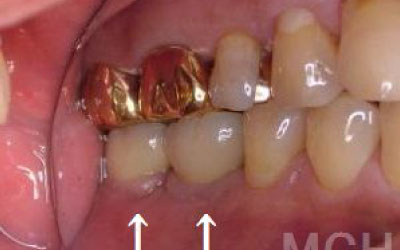

3 歯周病でインプラントが抜けるリスク

細菌(歯垢)の影響で、インプラントを支える歯ぐきや骨が痩せてしまうことがあります。

そのため、インプラント治療だけでなく、残っている天然歯の歯周病検査や治療もしっかり行うことが非常に重要です。

歯周病の進行度によりますが、インプラント治療は可能です。

ただし、まず歯周病の検査をしっかり行い、必要に応じて先に歯周病治療を行うことが欠かせません。

また、噛み合わせの調整や治療後の定期的なメンテナンスを行い、長持ちさせることも非常に重要です。